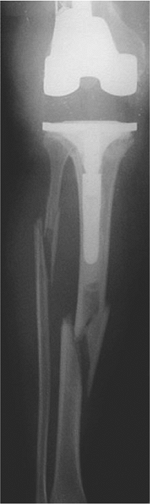

![]() |

|

Figure 45.2. Type II periprosthetic femur fracture originating around the tip of a loose stem.